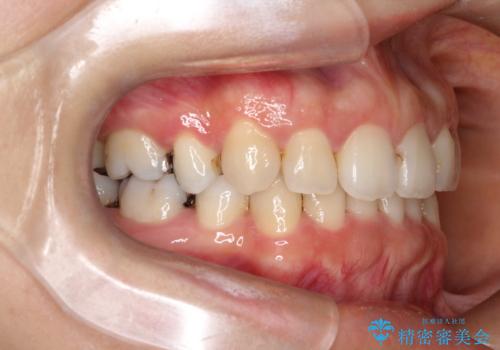

- 上下の歯の中心(正中)のズレと、口元の見た目を気にされて来院されました。精密な検査の結果、咬み合わせのバランスを整えながら、正中線を一致させる治療が必要と判断。患者様のご希望に合わせ、透明で目立ちにくいインビザライン(マウスピース矯正)による治療計画を立案しました。歯列全体を奥(遠心)へ移動させるためにゴムかけを併用。さらに、見た目を改善するため、既存の金属の被せ物をセラミッククラウンに交換することも治療計画に組み込みました。

今回の矯正治療では、透明なマウスピース型の装置インビザラインを使用しました。歯列を奥へ動かす遠心移動の効率を高めるため、患者様ご自身にゴムかけも行っていただきました。この併用によって、歯をより正確かつスムーズに動かすことができ、上下の歯の中心である正中線を一致させることが可能になりました。また、治療の最終段階では、以前から入っていた金属の被せ物を、天然歯に近い色合いのセラミッククラウンに交換。矯正治療と審美治療を組み合わせることで、機能的な咬み合わせの改善に加え、金属が見えない、より自然で美しい口元を獲得していただけました。